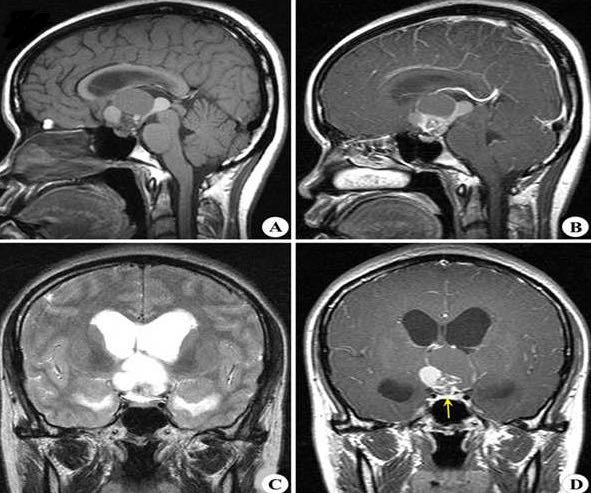

另外,以上提到的症状并不意味着孩子就得了肿瘤,还需要进一步的医学评估来排除脑瘤的可能性。通常情况下,诊断是根据放射学研究做出的,例如磁共振成像(MRI)用钆增强扫描大脑。颅咽管瘤在MRI扫描中有一个不同的表现:一个清晰的肿块,由实部和囊性部分组合而成。